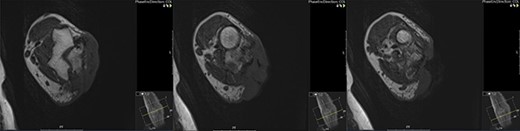

He was investigated with incisional biopsy of the lesion; four samples confirmed poorly differentiated cSCC. Further MRI imaging showed deep invasions of the cubital joint including, olecranon and ulna, and associated infiltration of the ulnar nerve and distal triceps (Figs 3 and 4). Positron emission tomography scan showed no distant metastases.

Cross-sectional MRI images demonstrating the position of the lesion and its infiltration into the joint space and deep tissues including the ulnar nerve.